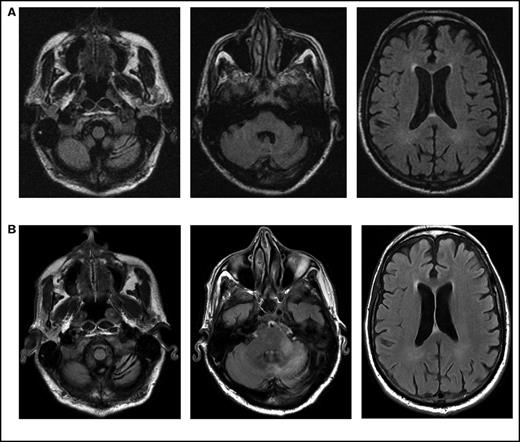

Presentation and imaging findings

Initial symptoms included limb weakness (5 patients), visual loss (3 patients), cognitive impairment/behavior change (4 patients), and a cerebellar syndrome (4 patients). Magnetic resonance imaging abnormalities were restricted to the cerebrum in 12 patients; 2 patients had abnormalities restricted to the cerebellum and brainstem (Figure 1), and 2 patients had abnormalities in both the cerebrum and the brainstem and cerebellum.

Serial imaging of a patient diagnosed with CLL. Cancer-directed therapy included >6 months of rituximab and idelalisib. (A) Initial magnetic resonance imaging performed 2 months after the onset of headaches and balance disturbance (gait instability and repeated falls) depicting the asymmetric atrophy of the left cerebellum, which was not present in imaging performed 7 months earlier (not depicted). Fluid-attenuated inversion recovery (FLAIR) signal abnormalities are not present elsewhere. (B) Imaging repeated 3 months later (1 month prior to death) showing the continued atrophy of the left cerebellum with new confluent areas of FLAIR signal throughout the left cerebellum and left cerebellar peduncle without enhancement. Again, no FLAIR signal abnormalities are seen in the cerebrum.